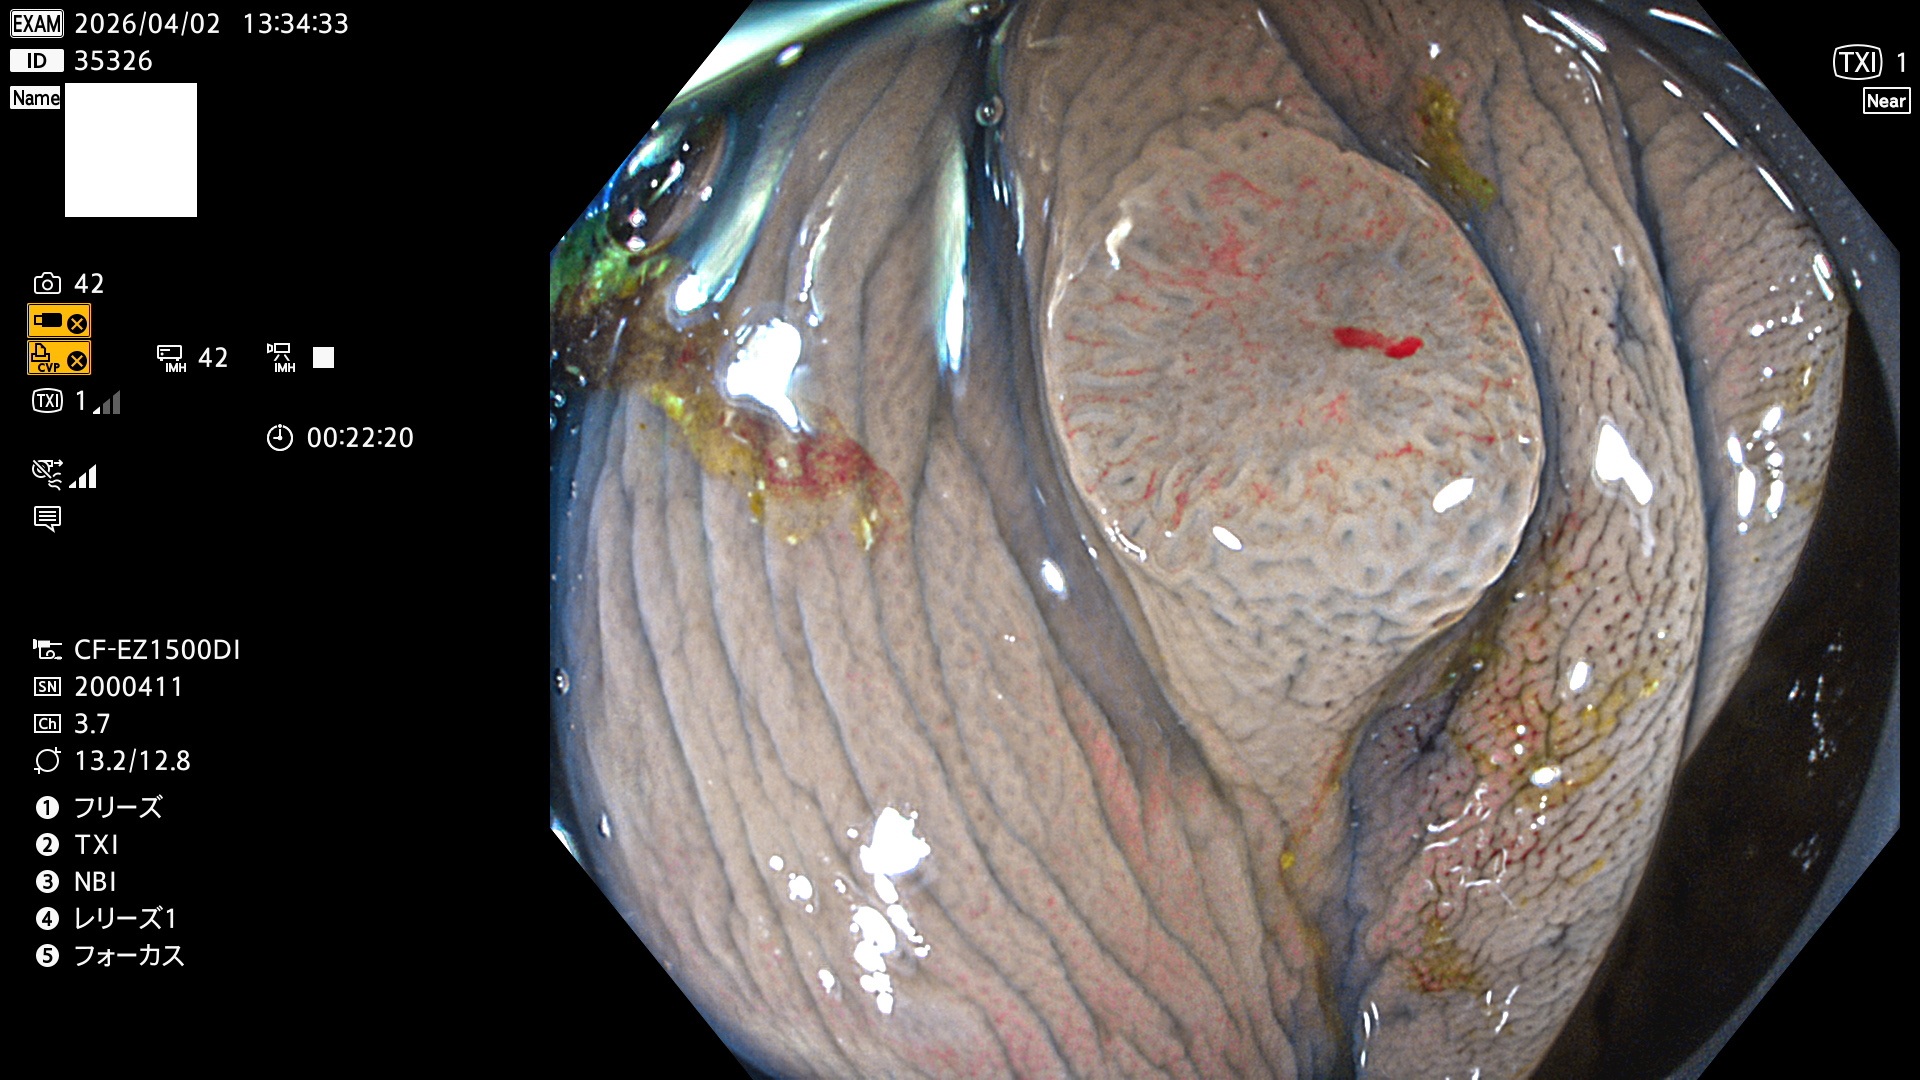

毎週の検査(木・金・土・日)に発見されたUbとUc型・腺腫を、その週の日曜の夜にUPし1週間、提示します。

2026年4月2日〜4月5日の4日間(40件)7個 (Uc_ADR=7個/40人=18%)